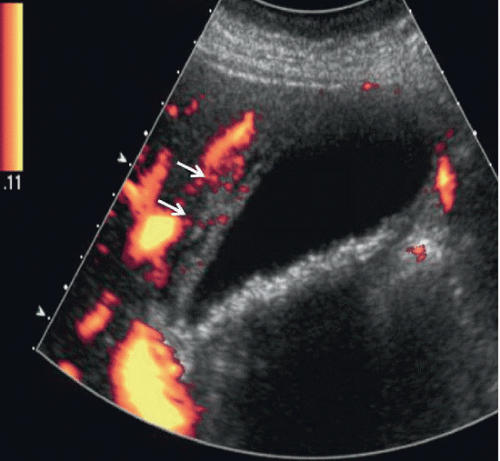

The virus persists in the liver in about 75% to 85% of those initially infected. Acute Cholecystitis | Radiology Key

Acute Cholecystitis | Radiology Key from radiologykey.com

When a person is first infected with the hepatitis b virus, it is called an acute infection (or a new infection)most healthy adults that are infected do not have any symptoms and are able to get rid of the virus without any problems hepatitis c chronic. Acute hepatitis is a clinical diagnosis and a normal imaging appearance of the liver does not exclude it 7.